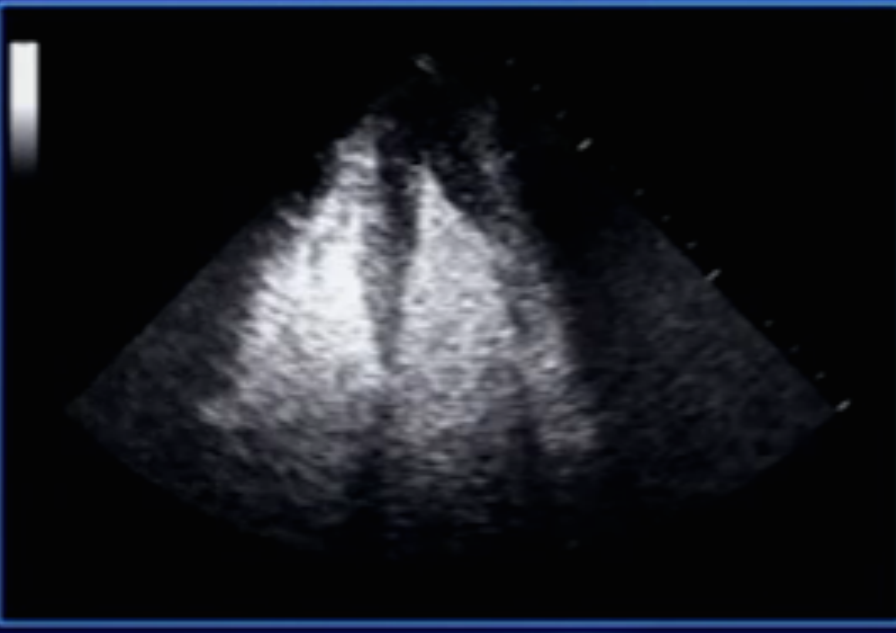

Diagnosis?

Apical HOCM (Spade shaped ventricle)